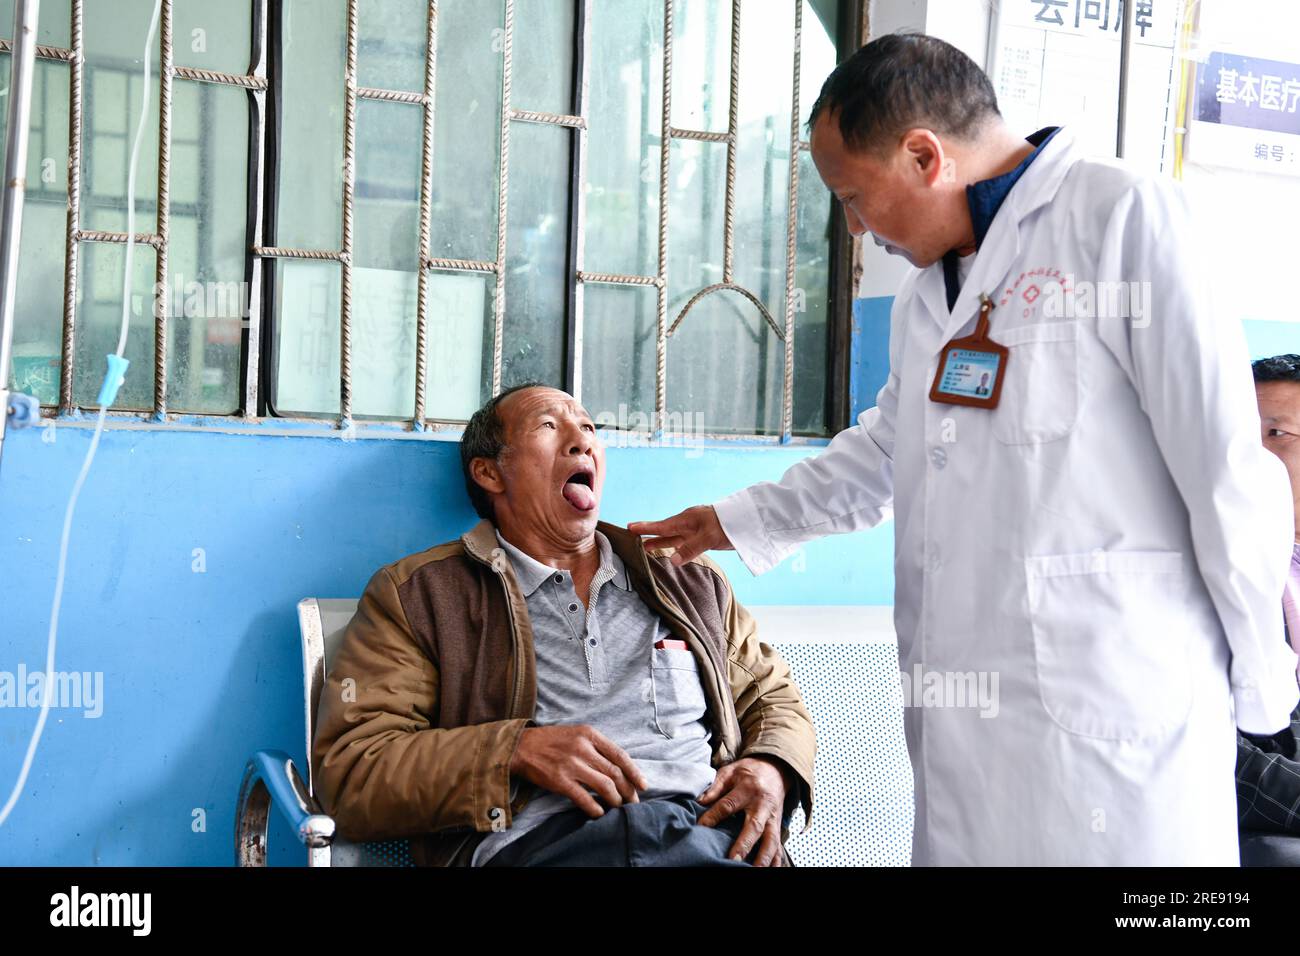

RM2RE9194–(230726) -- GUIYANG, 26. Juli 2023 (Xinhua) -- Zhu Daqing prüft den Zustand eines Patienten im Dorf Xinshui, Mazha Stadt Yi-Hui-Miao Autonomer Bezirk Weining, Provinz Guizhou im Südwesten Chinas, 19. Juli 2023. Zhu Daqing ist Landarzt im Dorf Xinshui, Mazha Stadt Yi-Hui-Miao Autonomer Kreis Weining. Zhu Daqing wurde in einer Familie mit Generationen von Ärzten geboren und war fest entschlossen, schon in jungen Jahren Arzt wie sein Vater zu sein, obwohl er aufgrund angeborener Abwesenheit der oberen Extremität im linken Unterarm behindert ist. Studierte traditionelle chinesische Medizin, Zhu Daqing studierte GUI

RM2RE919E–(230726) -- GUIYANG, 26. Juli 2023 (Xinhua) -- Zhu Daqing (L) prüft den medizinischen Bericht eines Patienten im Dorf Xinshui, Mazha Stadt Yi-Hui-Miao Autonomer Bezirk Weining, Provinz Guizhou im Südwesten Chinas, 19. Juli 2023. Zhu Daqing ist Landarzt im Dorf Xinshui, Mazha Stadt Yi-Hui-Miao Autonomer Kreis Weining. Zhu Daqing wurde in einer Familie mit Generationen von Ärzten geboren und war fest entschlossen, schon in jungen Jahren Arzt wie sein Vater zu sein, obwohl er aufgrund angeborener Abwesenheit der oberen Extremität im linken Unterarm behindert ist. Studierte traditionelle chinesische Medizin, Zhu Daqing schloss sein Studium ab

RM2RE9148–(230726) -- GUIYANG, 26. Juli 2023 (Xinhua) -- Zhu Daqing verabreicht einem älteren Patienten einen intravenösen Tropf im Patientenhaus im Dorf Xinshui, Mazha Stadt Yi-Hui-Miao Autonomer Bezirk Weining, Provinz Guizhou im Südwesten Chinas, 19. Juli 2023. Zhu Daqing ist Landarzt im Dorf Xinshui, Mazha Stadt Yi-Hui-Miao Autonomer Kreis Weining. Zhu Daqing wurde in einer Familie mit Generationen von Ärzten geboren und war fest entschlossen, schon in jungen Jahren Arzt wie sein Vater zu sein, obwohl er aufgrund angeborener Abwesenheit der oberen Extremität im linken Unterarm behindert ist. Studiert traditionelles Chi